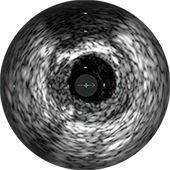

Изображение предоставил Аллен Джеремайас, врач. На изображении показано программное обеспечение SyncVision с функцией обнаружения устройств, которое позволяет легко визуализировать особенности проведения терапии.

Цифровой катетер для ВСУЗИ Eagle Eye Platinum

Система для визуализации и ко-регистрации данных SyncVision

ВСУЗИ